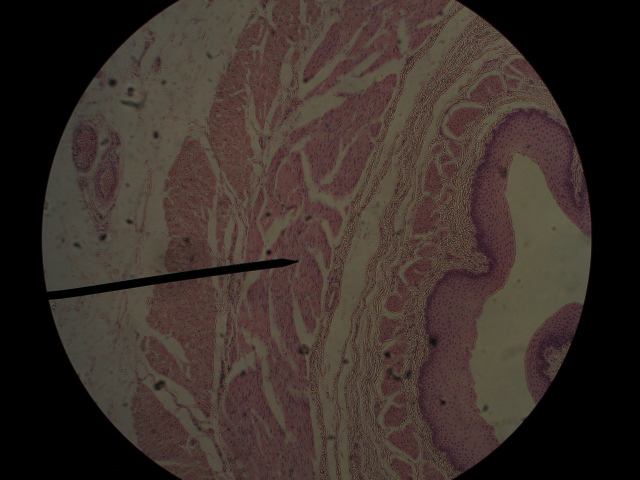

Identify this accessory organ,  | appendix |